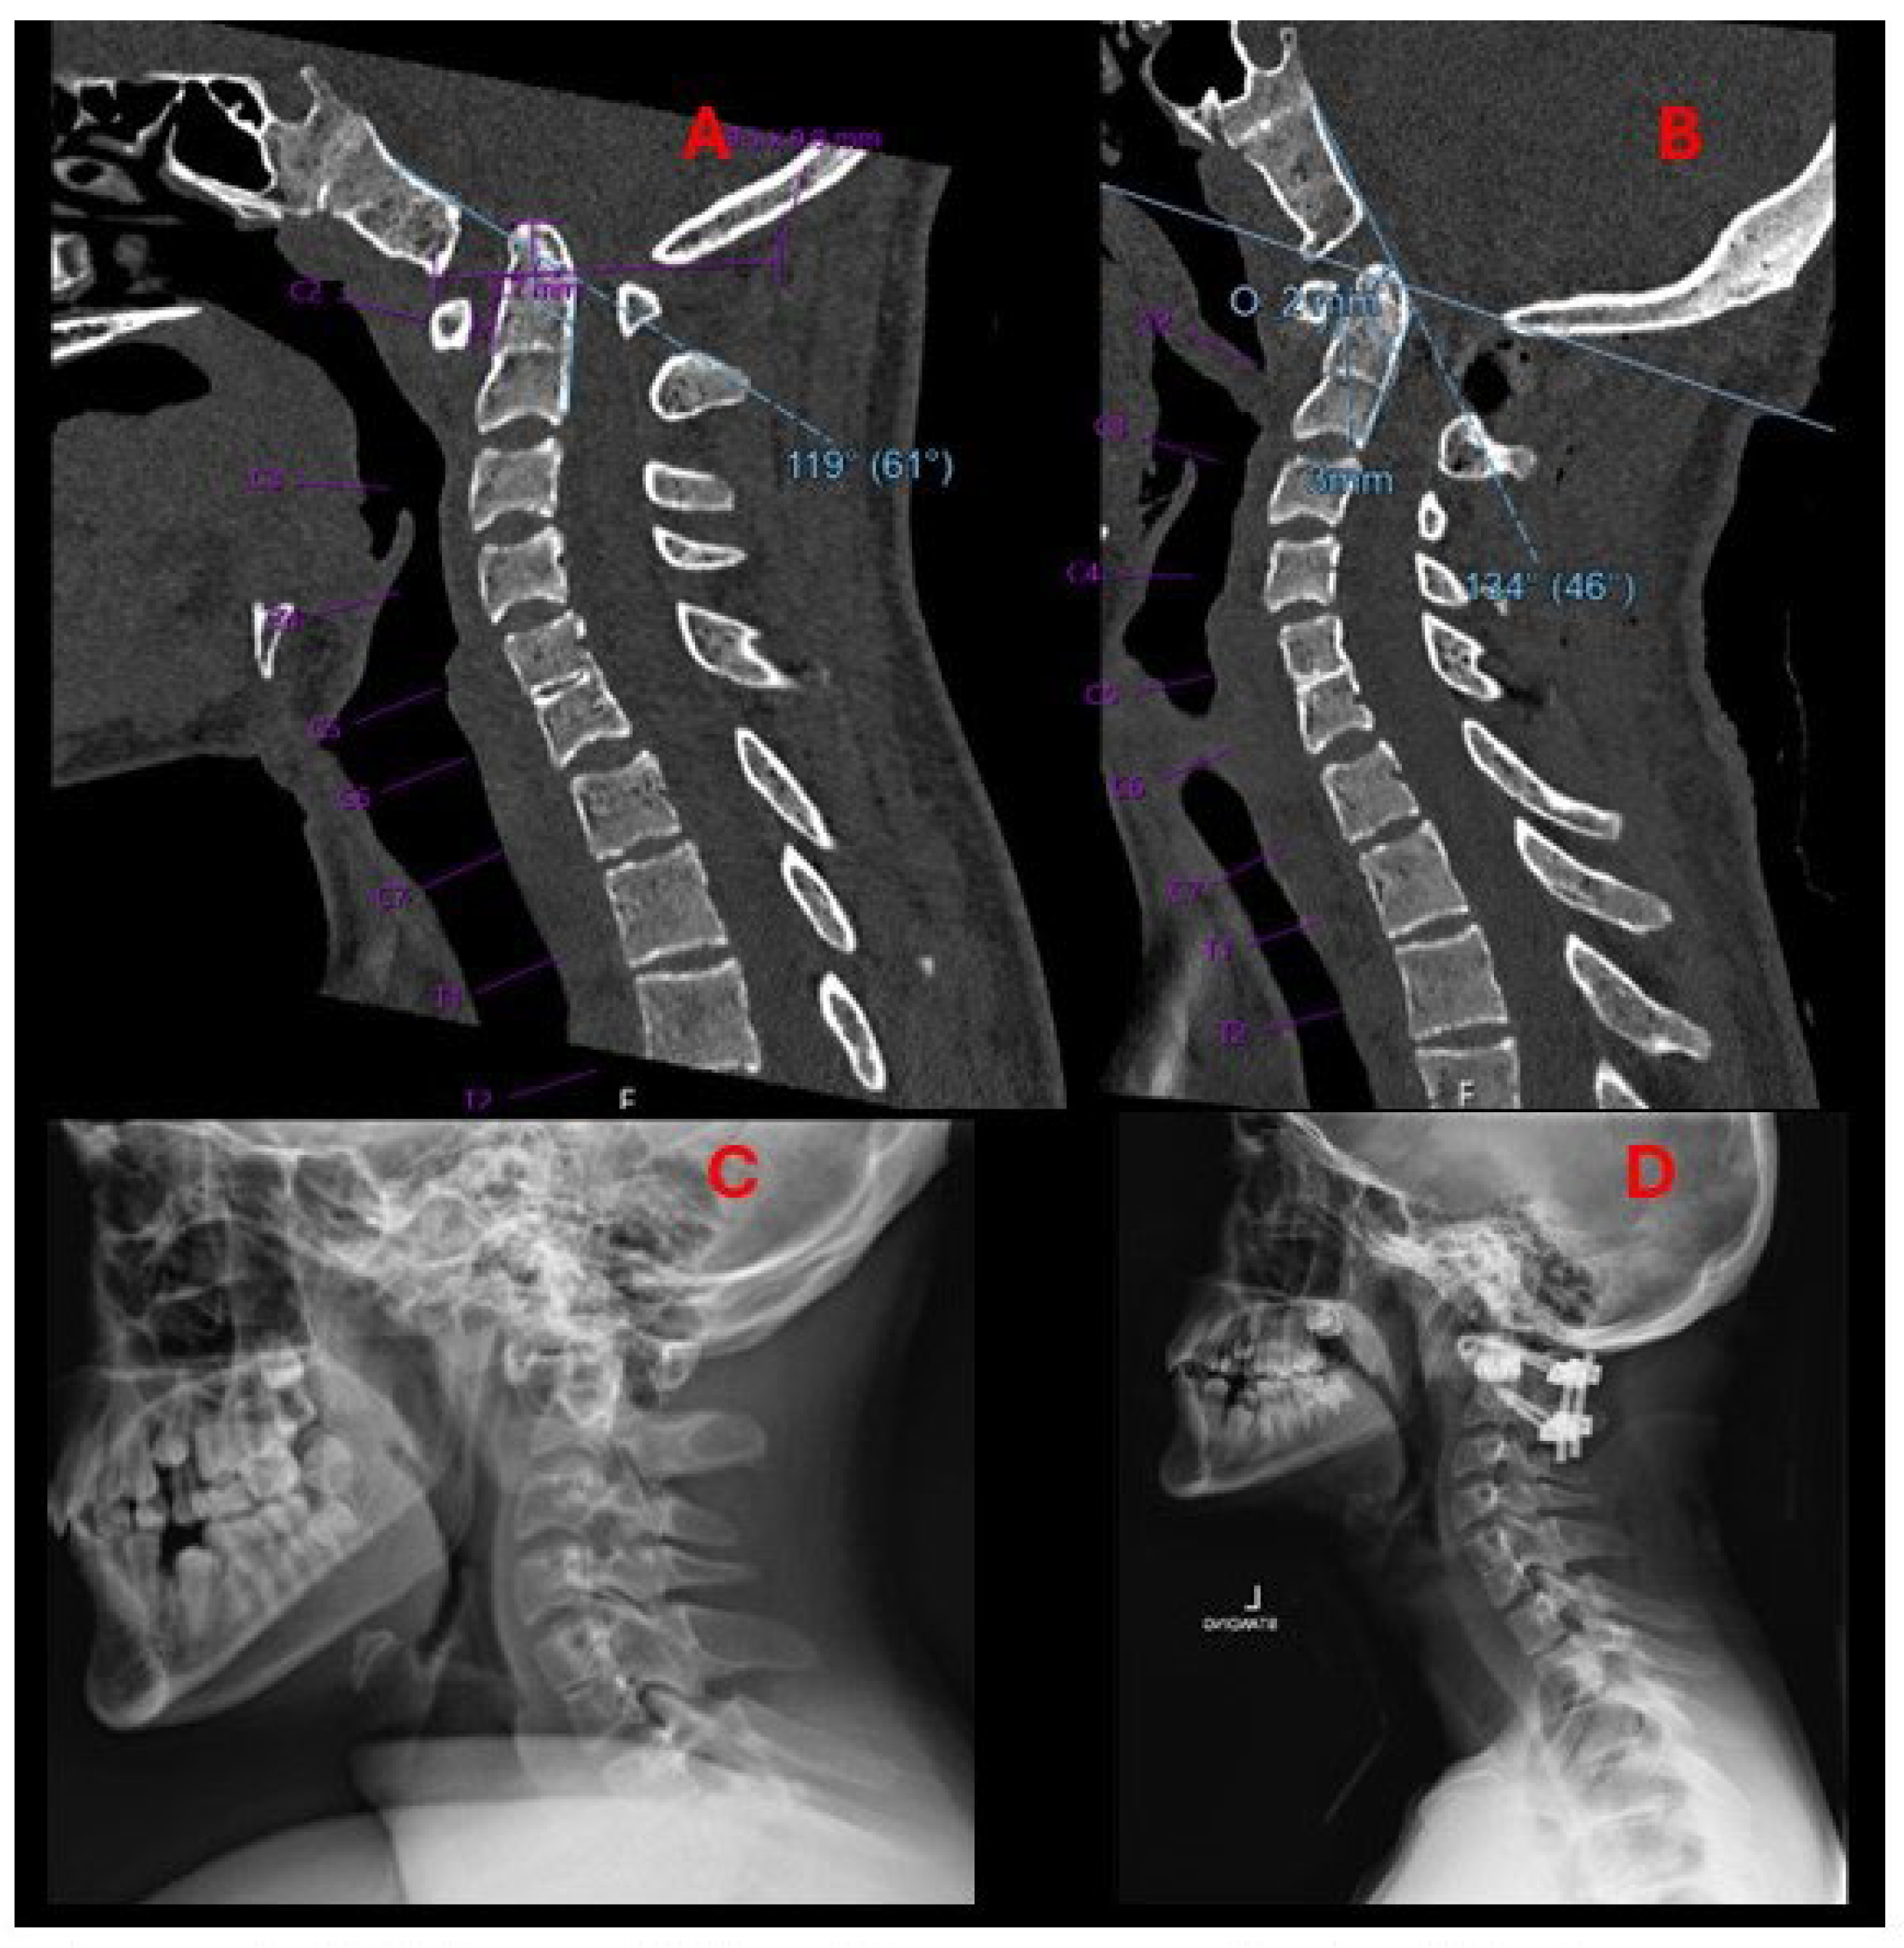

2.2. Imaging and Diagnosis

4. Results